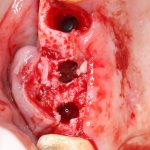

Возвращаемся к основной операционной области. Еще раз посмотрим на альвеолярный гребень, поофигеваем от его ширины и моих грандиозных планов:

Я зафиксировал костный блок практически без адаптации на несколько винтов. Обрати внимание, что винты находятся в зоне, где не планируется установка имплантатов. Фиксация должна быть надежной, поскольку мне еще предстояла подготовка лунок для имплантатов. Трех винтов для этого вполне достаточно.

Глянем на то, что получилось:

Осталось адаптировать костный блок (убрать острые края), проверить его фиксацию и, при необходимости, добавить винты. Десятисекундное дело.